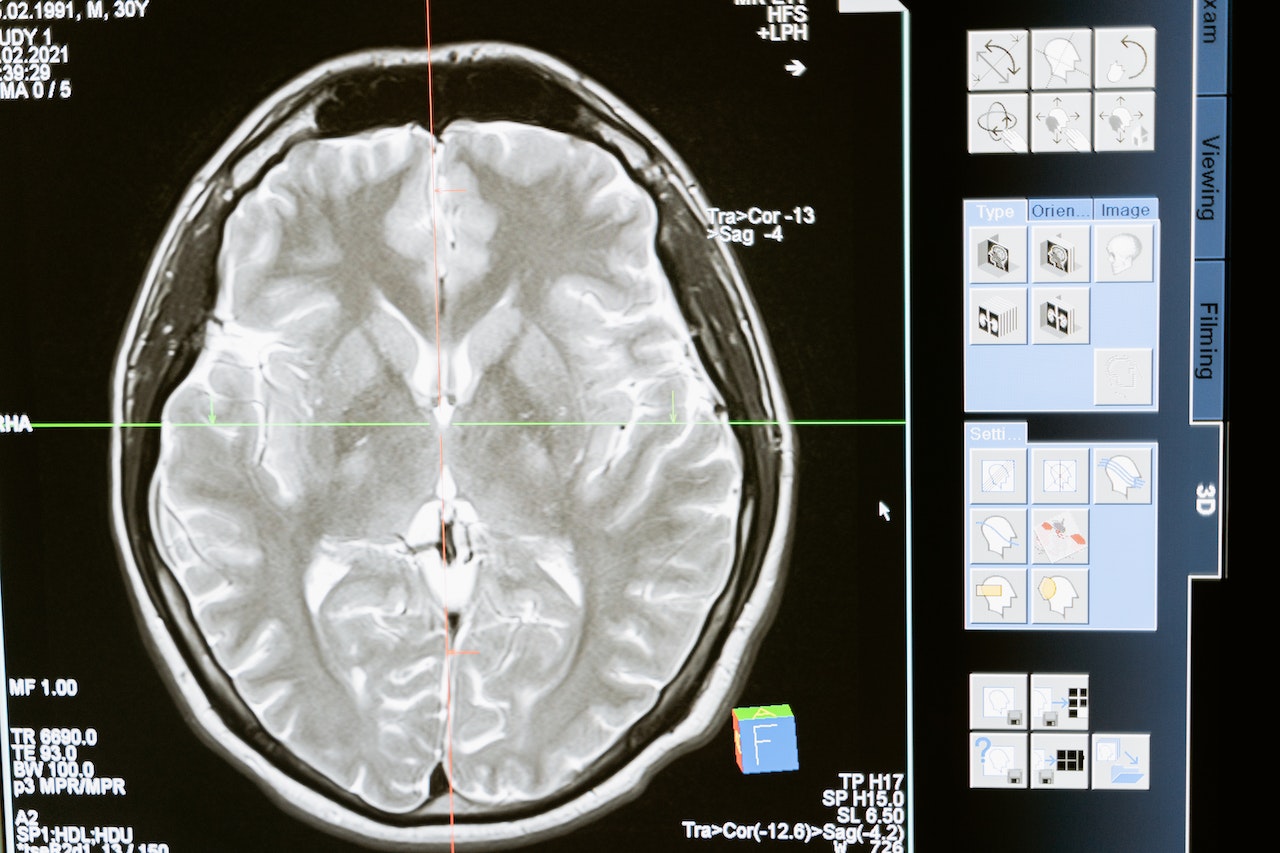

Escáner cerebral

Es probable que hayas escuchado en algún momento de tu vida el término demencia frontotemporal. Este es un término general para un grupo de trastornos cerebrales que afectan principalmente los lóbulos frontal y temporal del cerebro.

En este artículo, te contamos mucho más acerca de la demencia frontotemporal: fases, síntomas y prevención, entre otros.